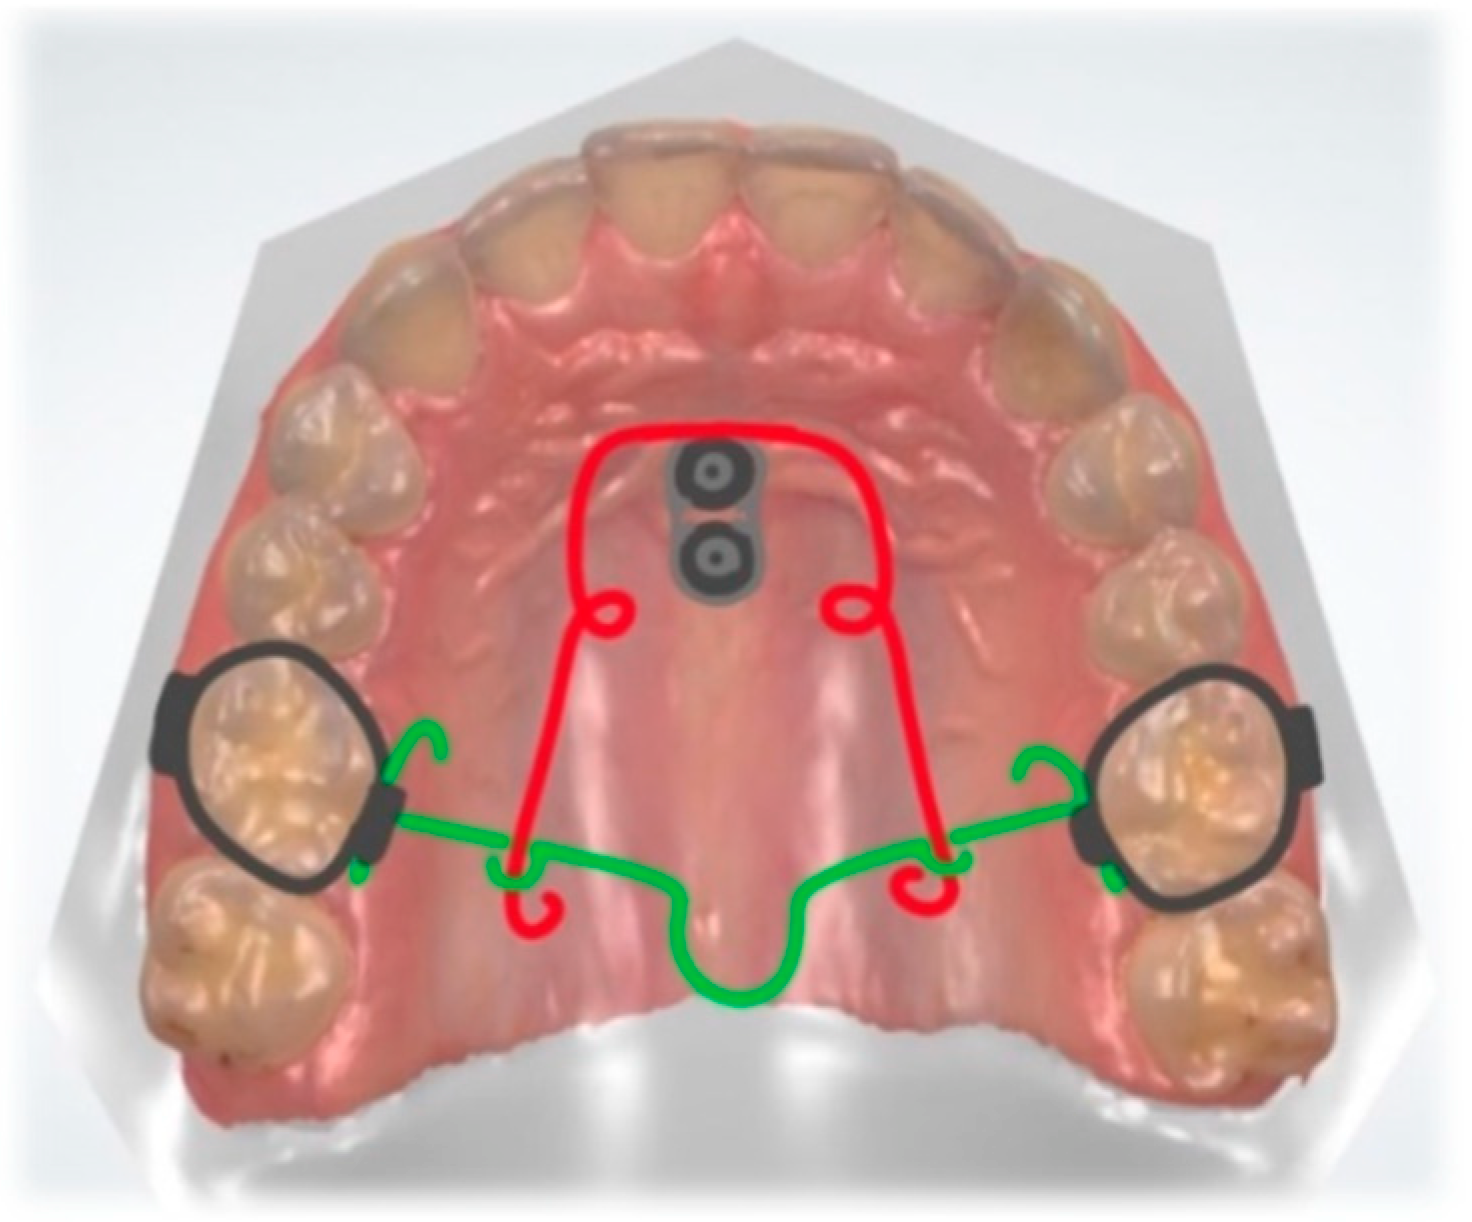

10. Molar Uprighting

13. Molar Distalization